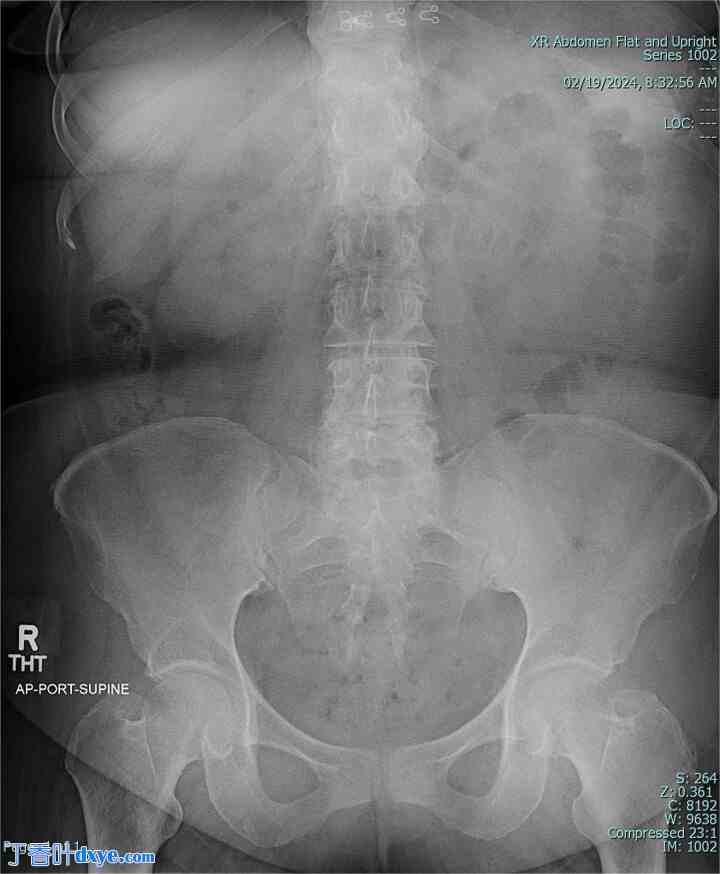

一名 67 岁的女性患者,既往病史仅与剖腹产有关,出现 1 周间歇性腹痛、腹胀和恶心呕吐。生命体征在正常范围内。体格检查发现腹部柔软、无膨胀,右下腹压痛。实验室检查未发现异常。放射影像学(图 1 和图 2)显示小肠梗阻正在发展。

图 1。

术前腹部 X 光片,显示小肠梗阻。